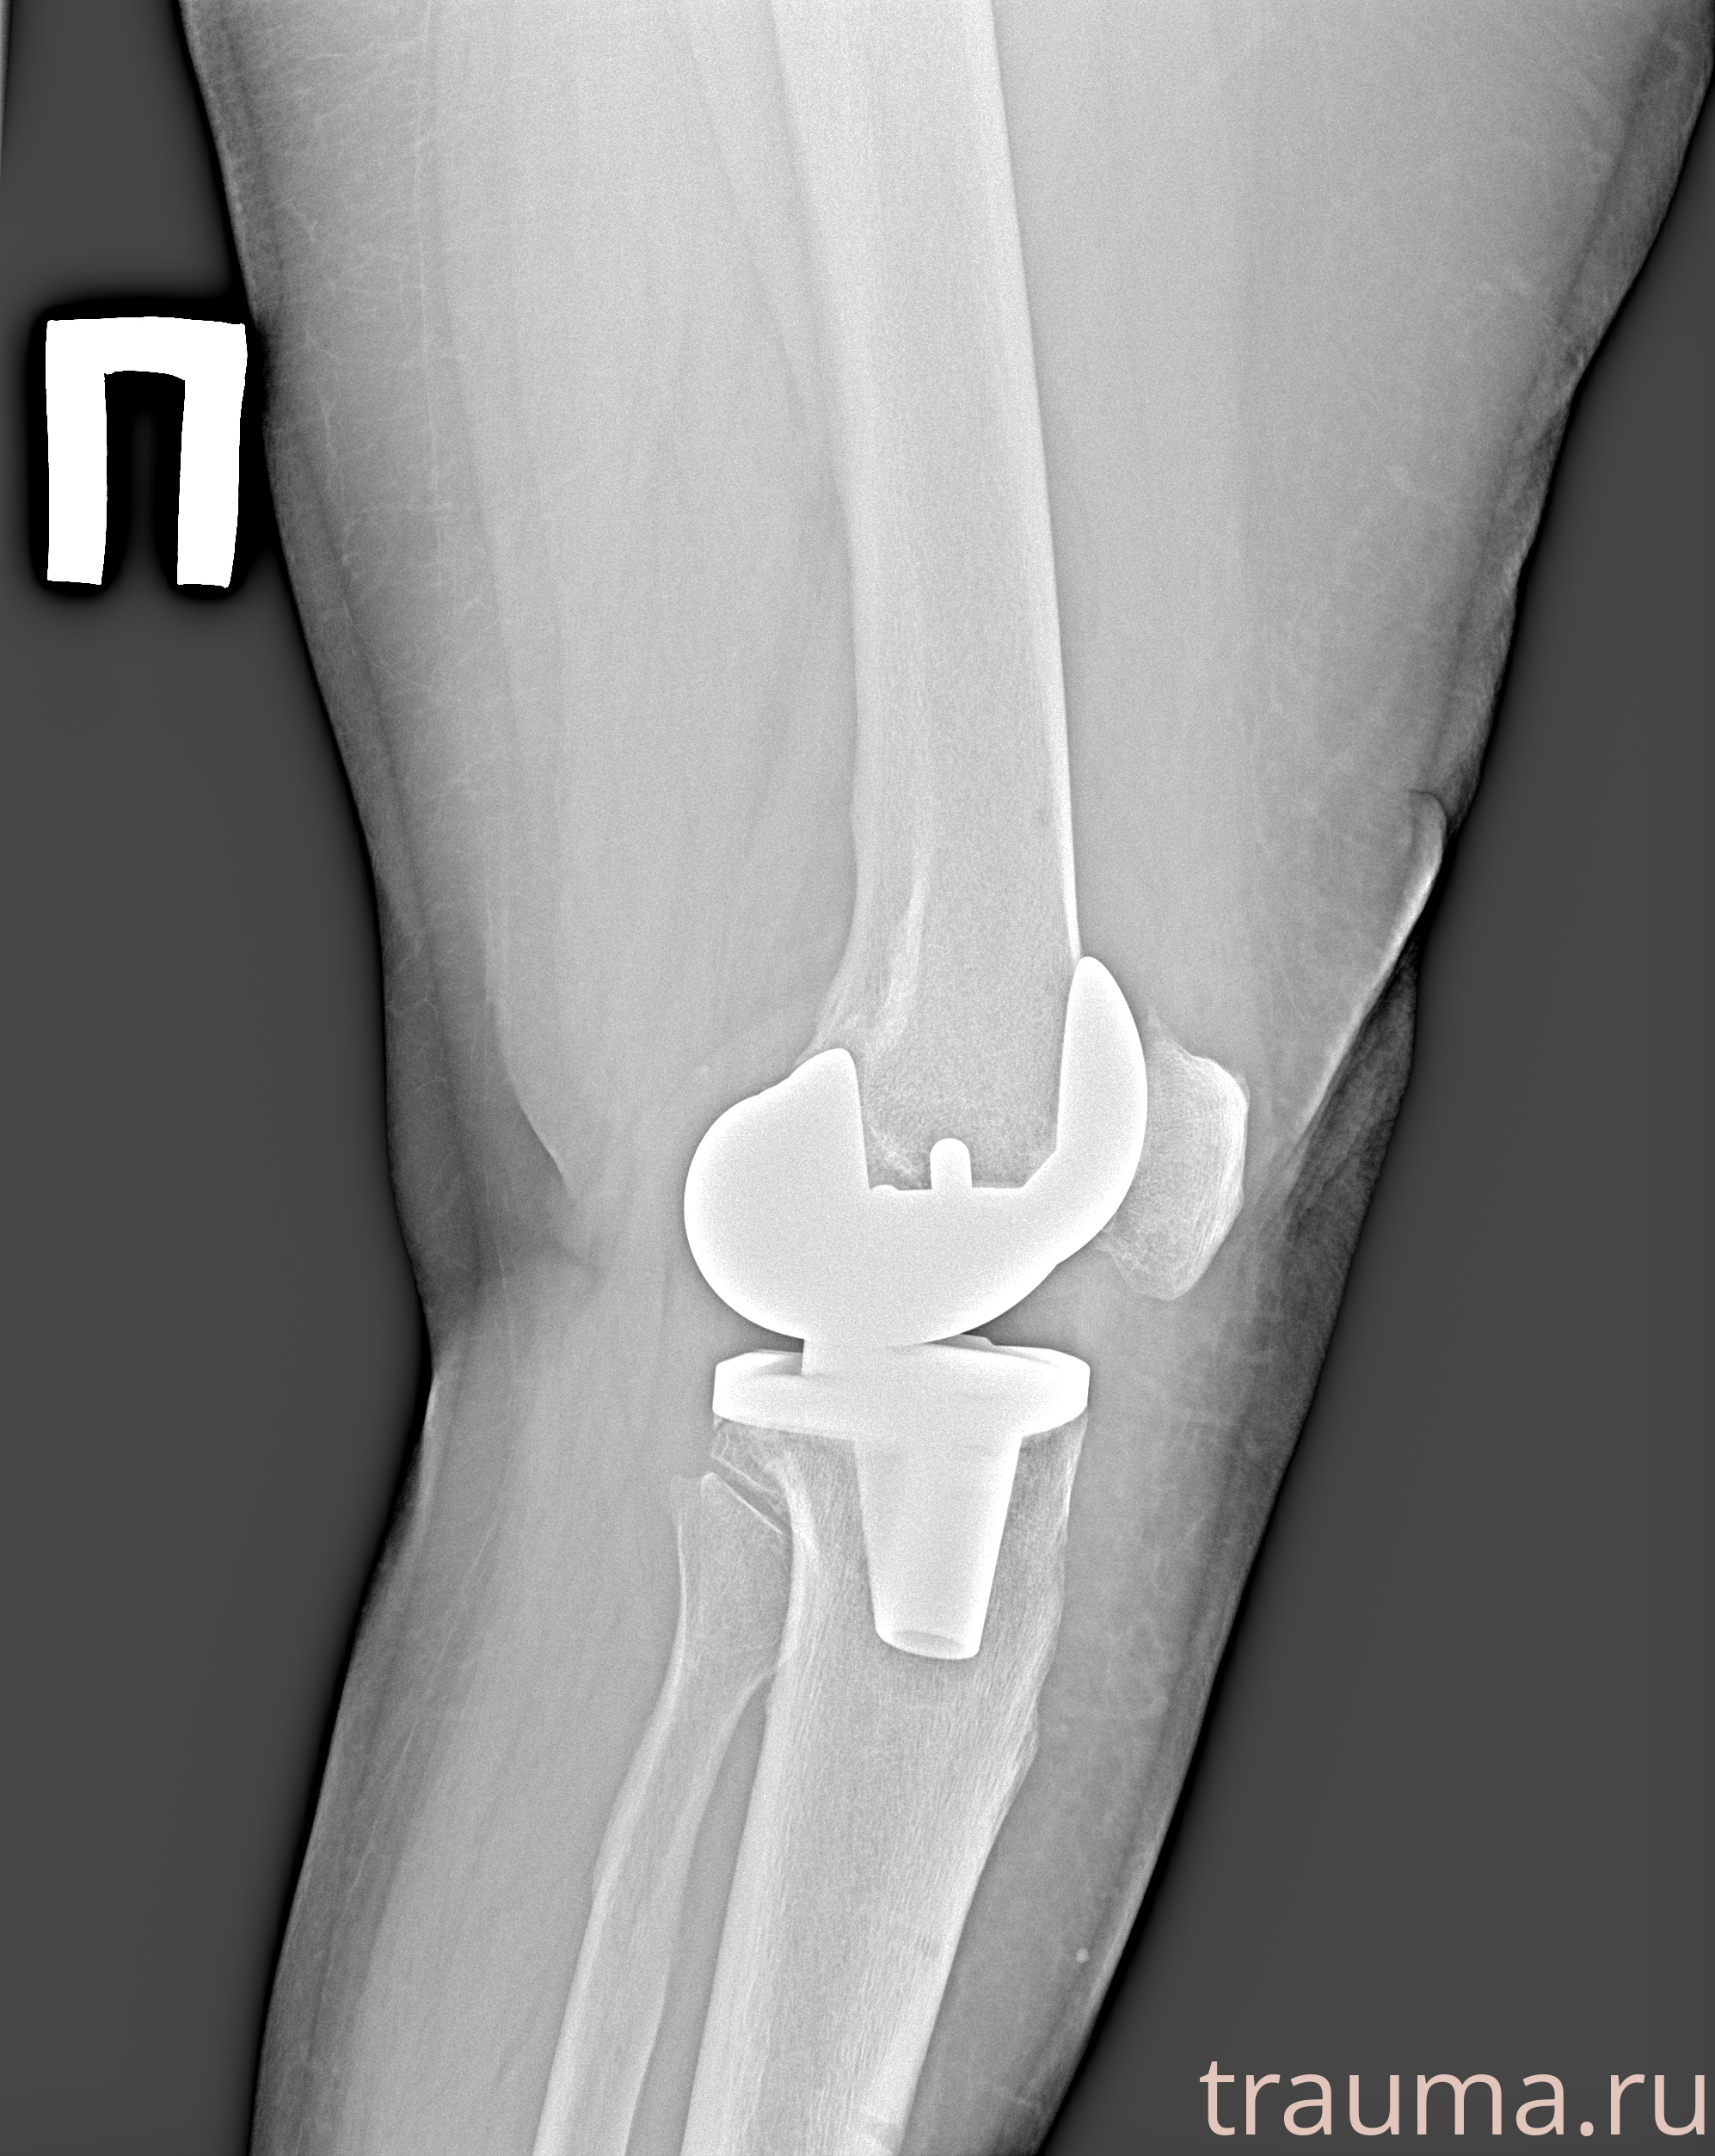

Рентгенограммы

Рентген на дому: по вашему адресу приезжает врач-рентгенолог, травматолог-ортопед с мобильным рентгеновским аппаратом, проводит диагностику травмы или заболевания, делает необходимые рентгенограммы, дает рекомендации по дальнейшему лечению. Получить качественные снимки в домашних условиях возможно благодаря уникальной методике, разработанной МосРентген Центром для института  Склифосовского